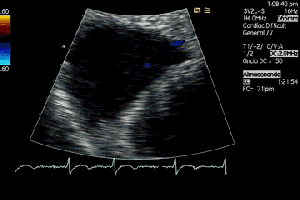

142. Ecocardiografía.Plano Apical 4 cámaras